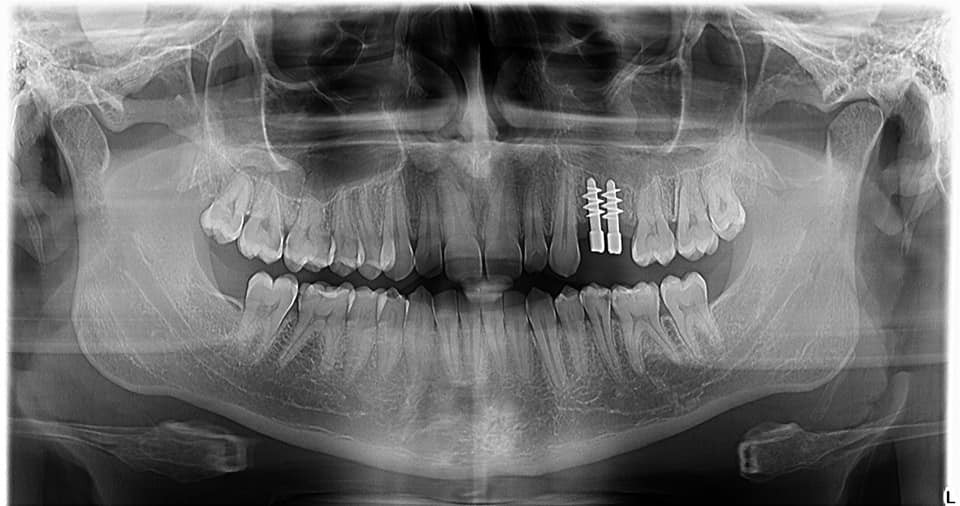

Implant dentar